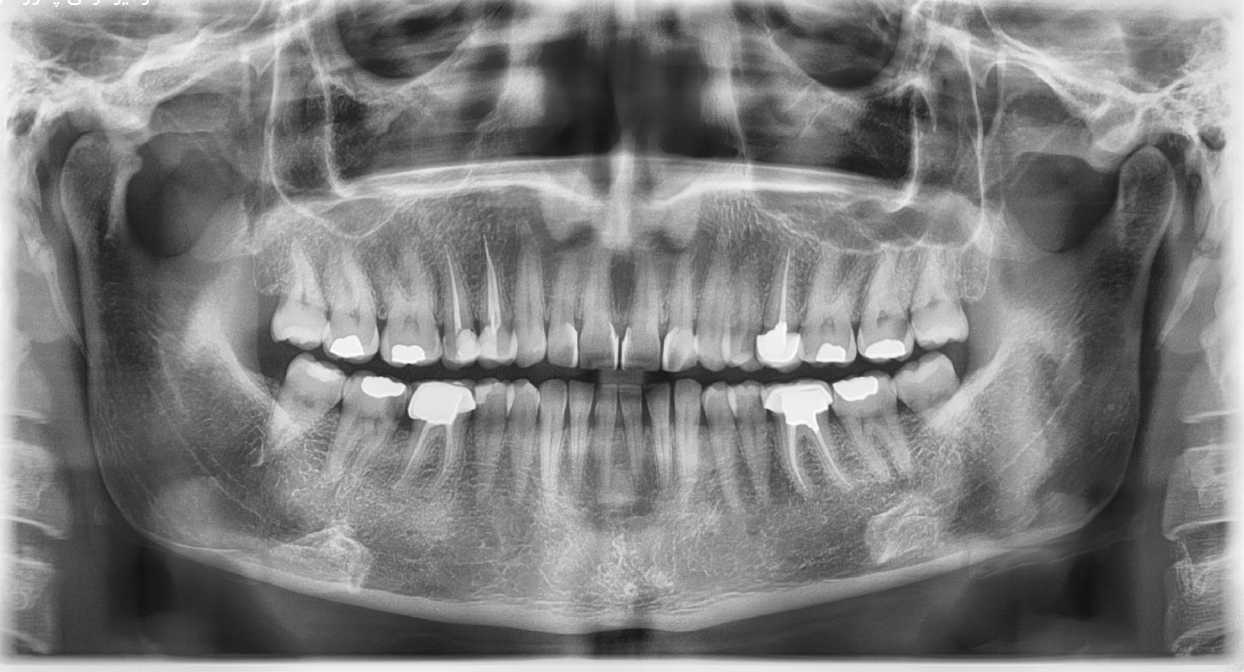

- رادیوگرافی پانورامیک